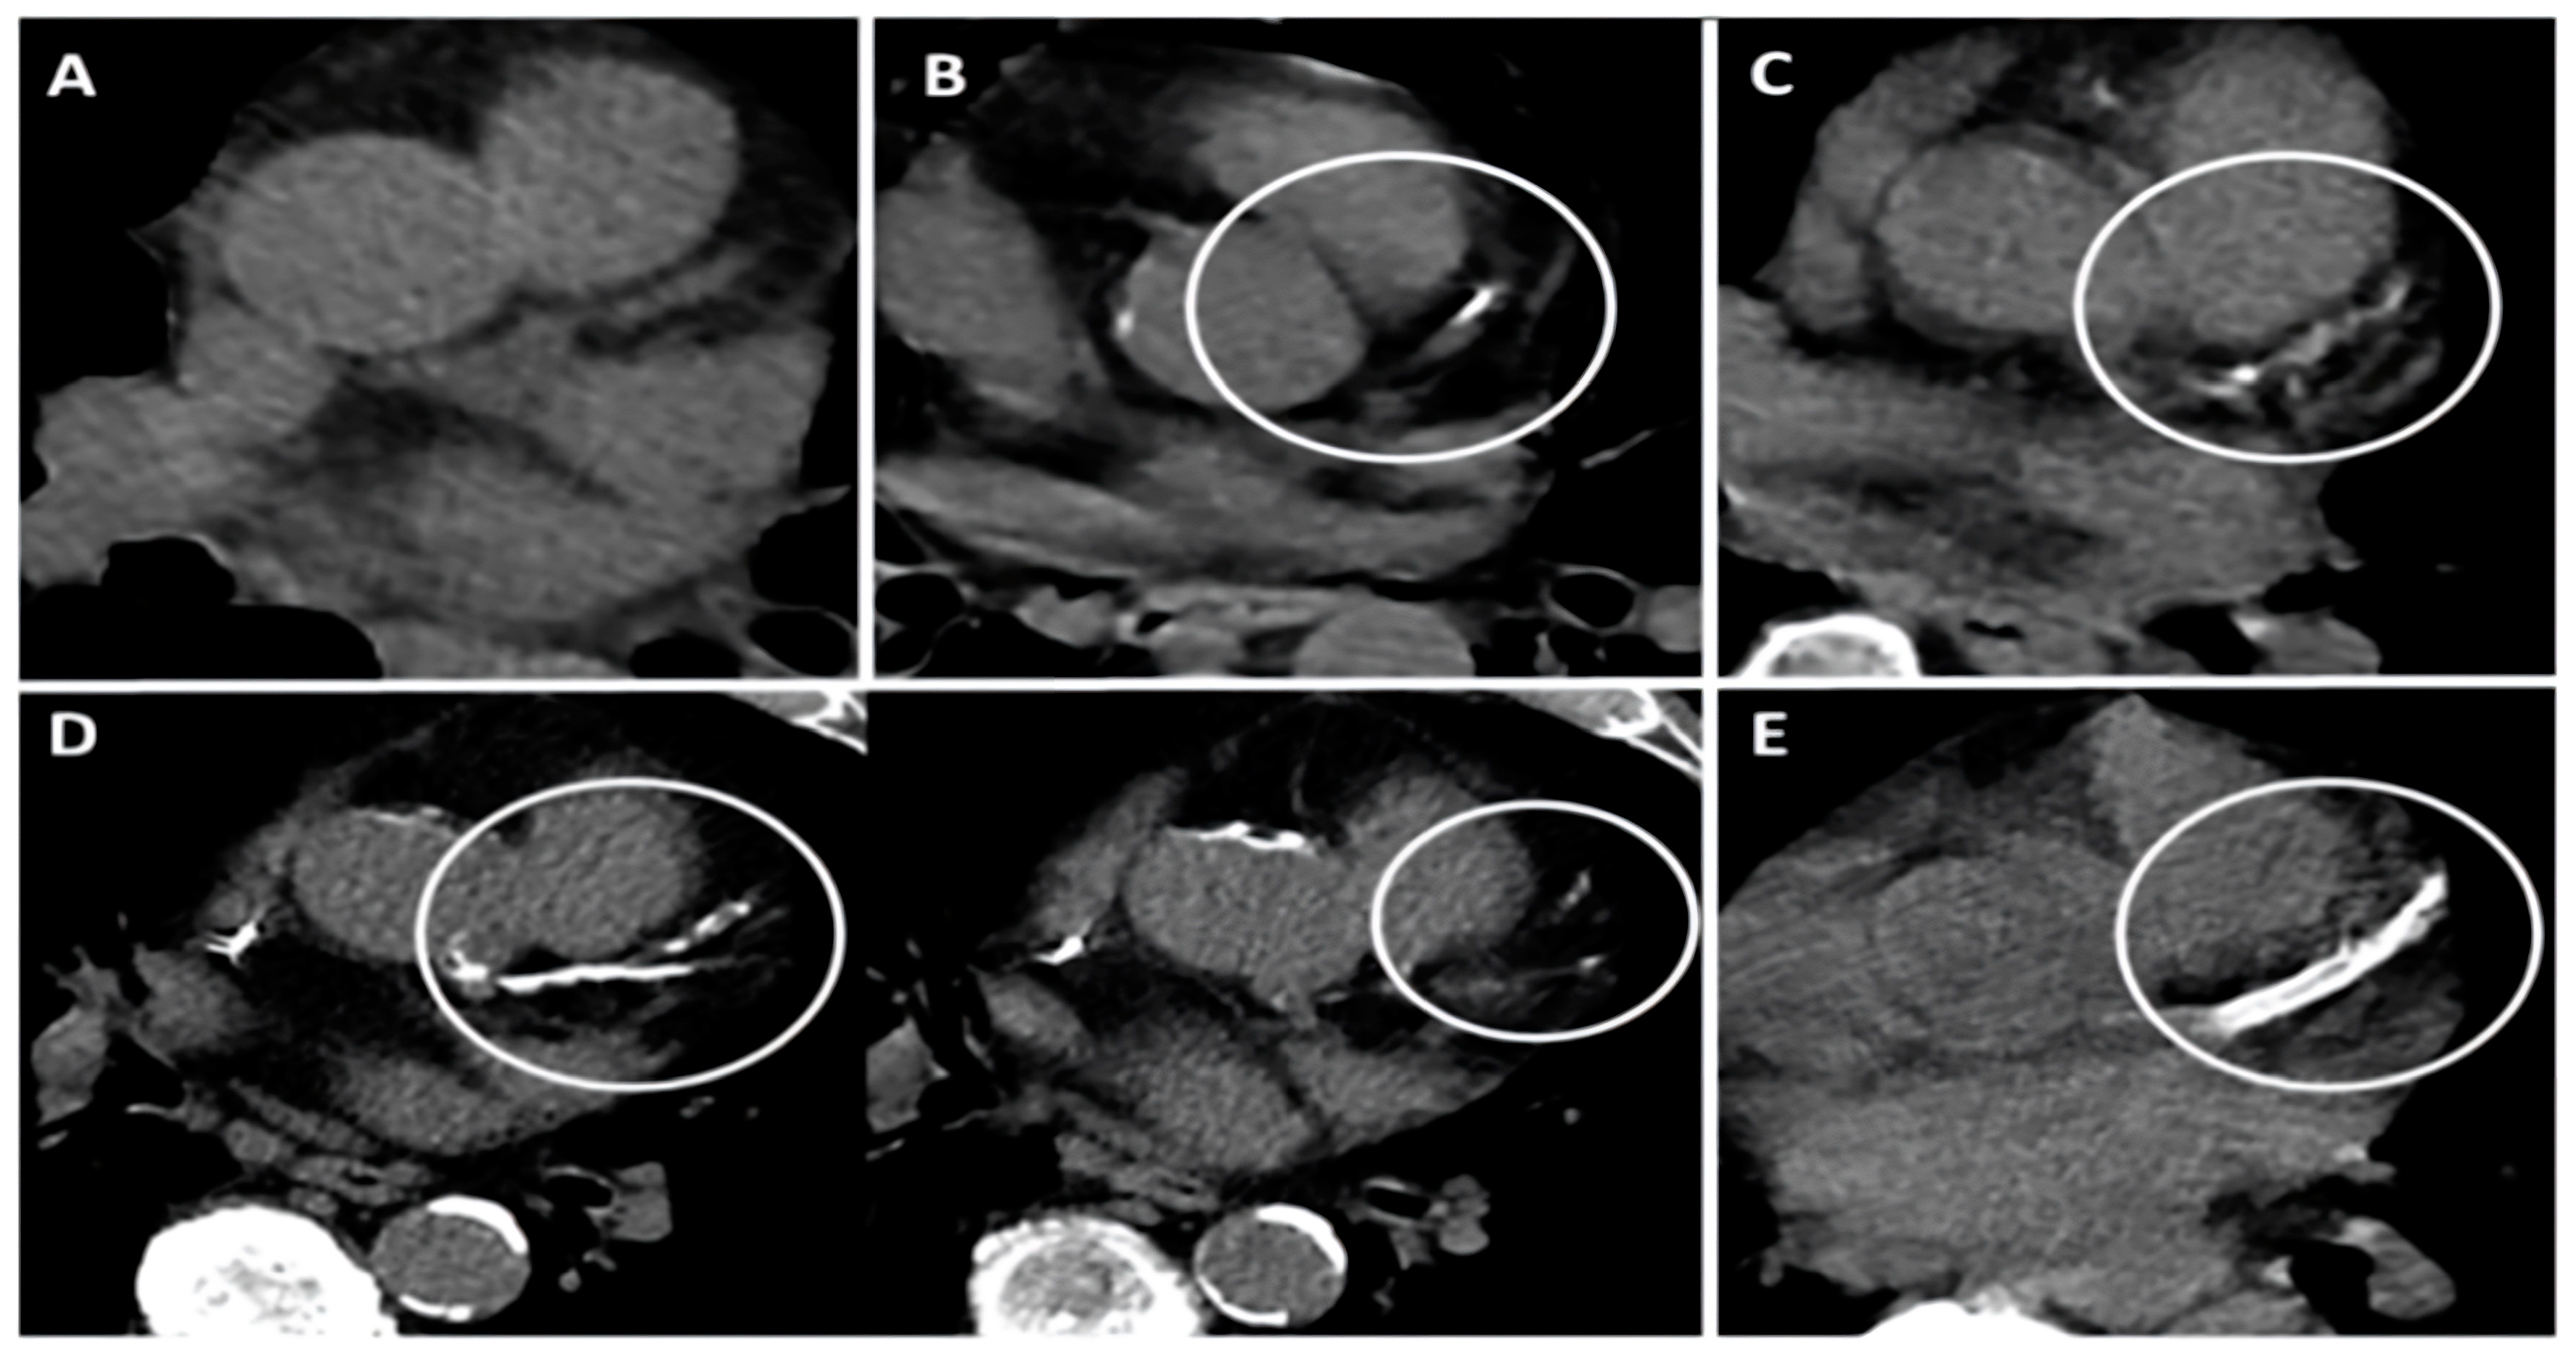

- Shemesh, J.; Henschke, C.I.; Shaham, D.; Yip, R.; Farooqi, A.O.; Cham, M.D.; McCauley, D.I.; Chen, M.; Smith, J.P.; Libby, D.M.; et al. Ordinal scoring of coronary artery calcifications on low-dose CT scans of the chest is predictive of death from cardiovascular disease. Radiology 2010, 257, 541–548. [Google Scholar] [CrossRef] [PubMed]

| Thorax CT-CACS | 3.5 (1–6.7) | 0 (0–3) | <0.001 |

| Thorax CT-CACS +, n (%) | 84 (%81) | 100 (%45) | <0.001 |

| Thorax CT—aortic calcification +, n (%) | 86 (%82.7) | 103 (%46.6) | <0.001 |

| Thorax CT CAC + aortic calcification + | 5.28 | 3.13–8.91 | <0.001 | 3.85 | 1.69–8.78 | 0.001 |

| C | CACS + Aort calcification + | 1 point |